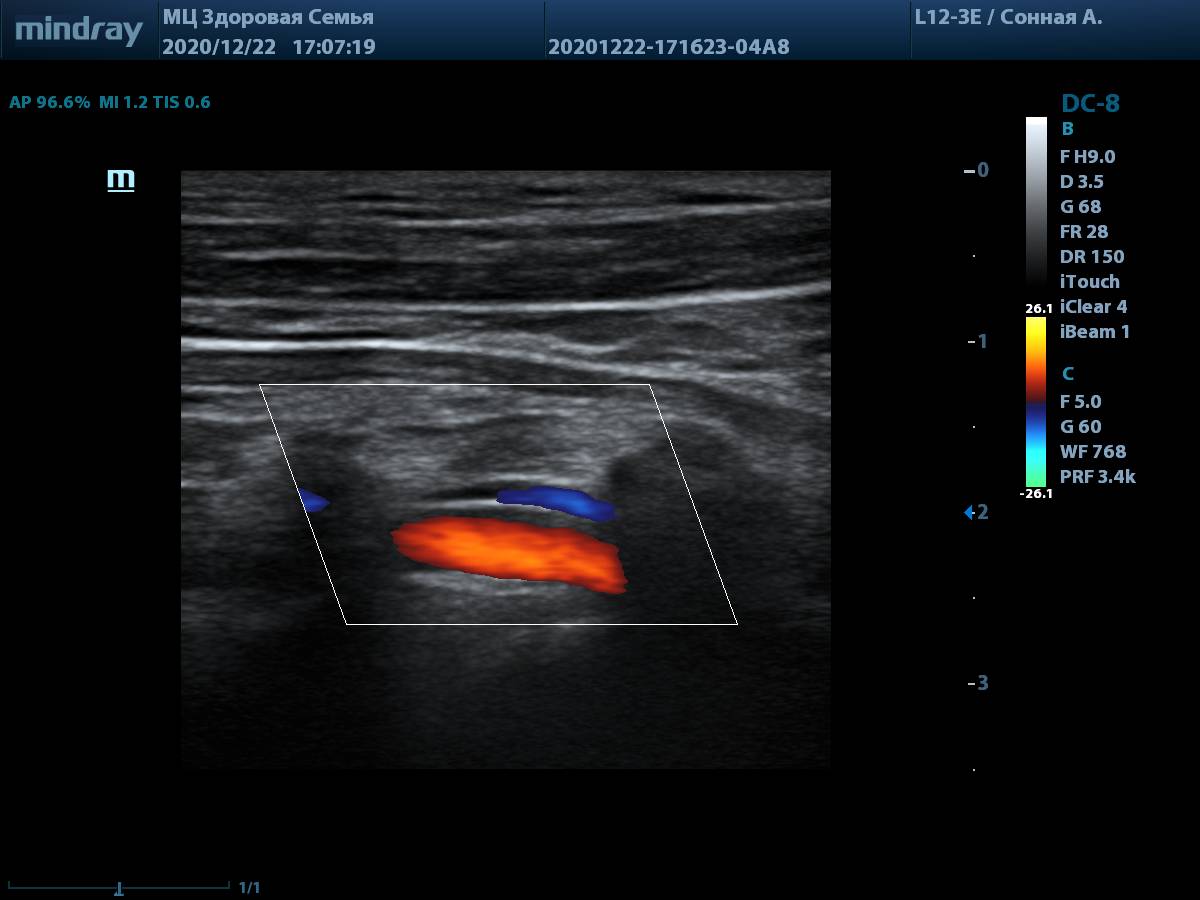

8. Общая сонная артерия (L12-3E) с использованием системы автоматического измерения комплекса интима-медиа, согласно международным стандартам.

Общая сонная артерия, авто IMT